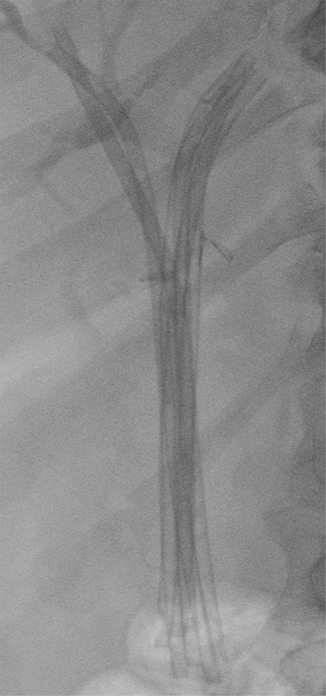

Fig. 8.6

Plain X-ray after placement of six plastic stents for postoperative biliary stricture. Metal clips placed near the hilum during laparoscopic cholecystectomy are also visible. This is the same patient in Fig. 8.7a

The patient underwent ERCP that confirmed a type III Bismuth and Lazorthes stricture and during the first treatment only two plastic stents were placed (Fig. 8.7a and b). The patient underwent three more ERCPs every 3 months over a period of 1 year with multiple plastic stents exchanged (Fig. 8.7c) until complete resolution of the stricture (Fig. 8.7d).